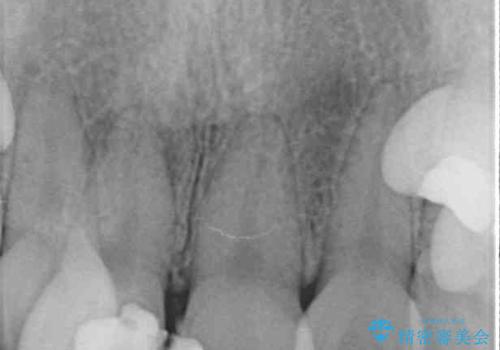

- 放置した虫歯や抜いたままの奥歯、前歯のデコボコを気にして来院された患者様です。

口元の突出感は少なく、下顎の叢生は軽微なものであったので、叢生の強い上顎左右の小臼歯を1本ずつ抜歯し、ワイヤー装置にて矯正治療を行うこととしました。

矯正治療を行う前に、根管治療の必要な上顎前歯と下顎大臼歯の根管治療を行い、矯正治療の途中で下顎の欠損部にインプラント埋入することとし、矯正治療後に補綴治療を行うこととしました。

矯正治療をしたいと思っていたが、放置している虫歯が多いため、どこに相談に行けば良いのか分からずにいたそうですが、当院の総合歯科診療を見て来院されたそうです。

矯正治療中にインプラント埋入を行うなど、余計な時間や無駄のない治療を行うことができました。